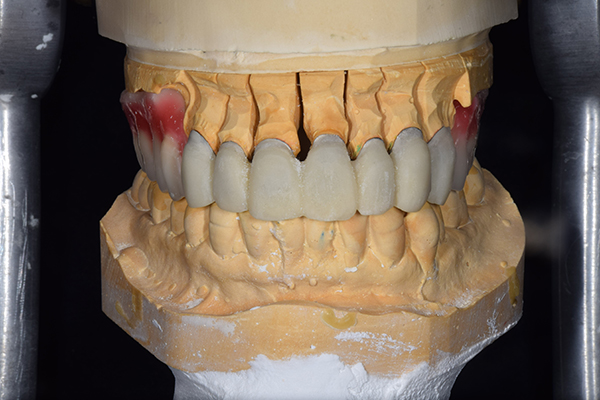

7.歯を並べる

噛み合わせをが決定したら、咬合器という装置に模型をくっつけて、歯を並べていきます。自費の入れ歯の場合こちらを歯科医師で行います。保険の入れ歯の場合は模型を技工所に送り、技工士さんに歯を並べてもらいます。最終的な入れ歯を作る気持ちで並べていきますが、どうしても噛み合わせの誤差が模型とお口の中とでは生じてしまいますので、歯をならべたものを患者様のお口の中にいれて確認していきます。

確認することとしては、歯と患者様のお顔の調和、噛み合わせ、見た目、フィット感などです。 こうすることで、患者様に合った精密な入れ歯を作ることができます。

歯を並べた後、かぶせ物のフレーム作ってもらいました。先に歯を並べて理想の位置を決めておくことが大切です。

噛み合わせチェックでしっかり奥歯で噛めるようにし、 歯を並べます。 その後、それに合わせて前歯を作っていきます。